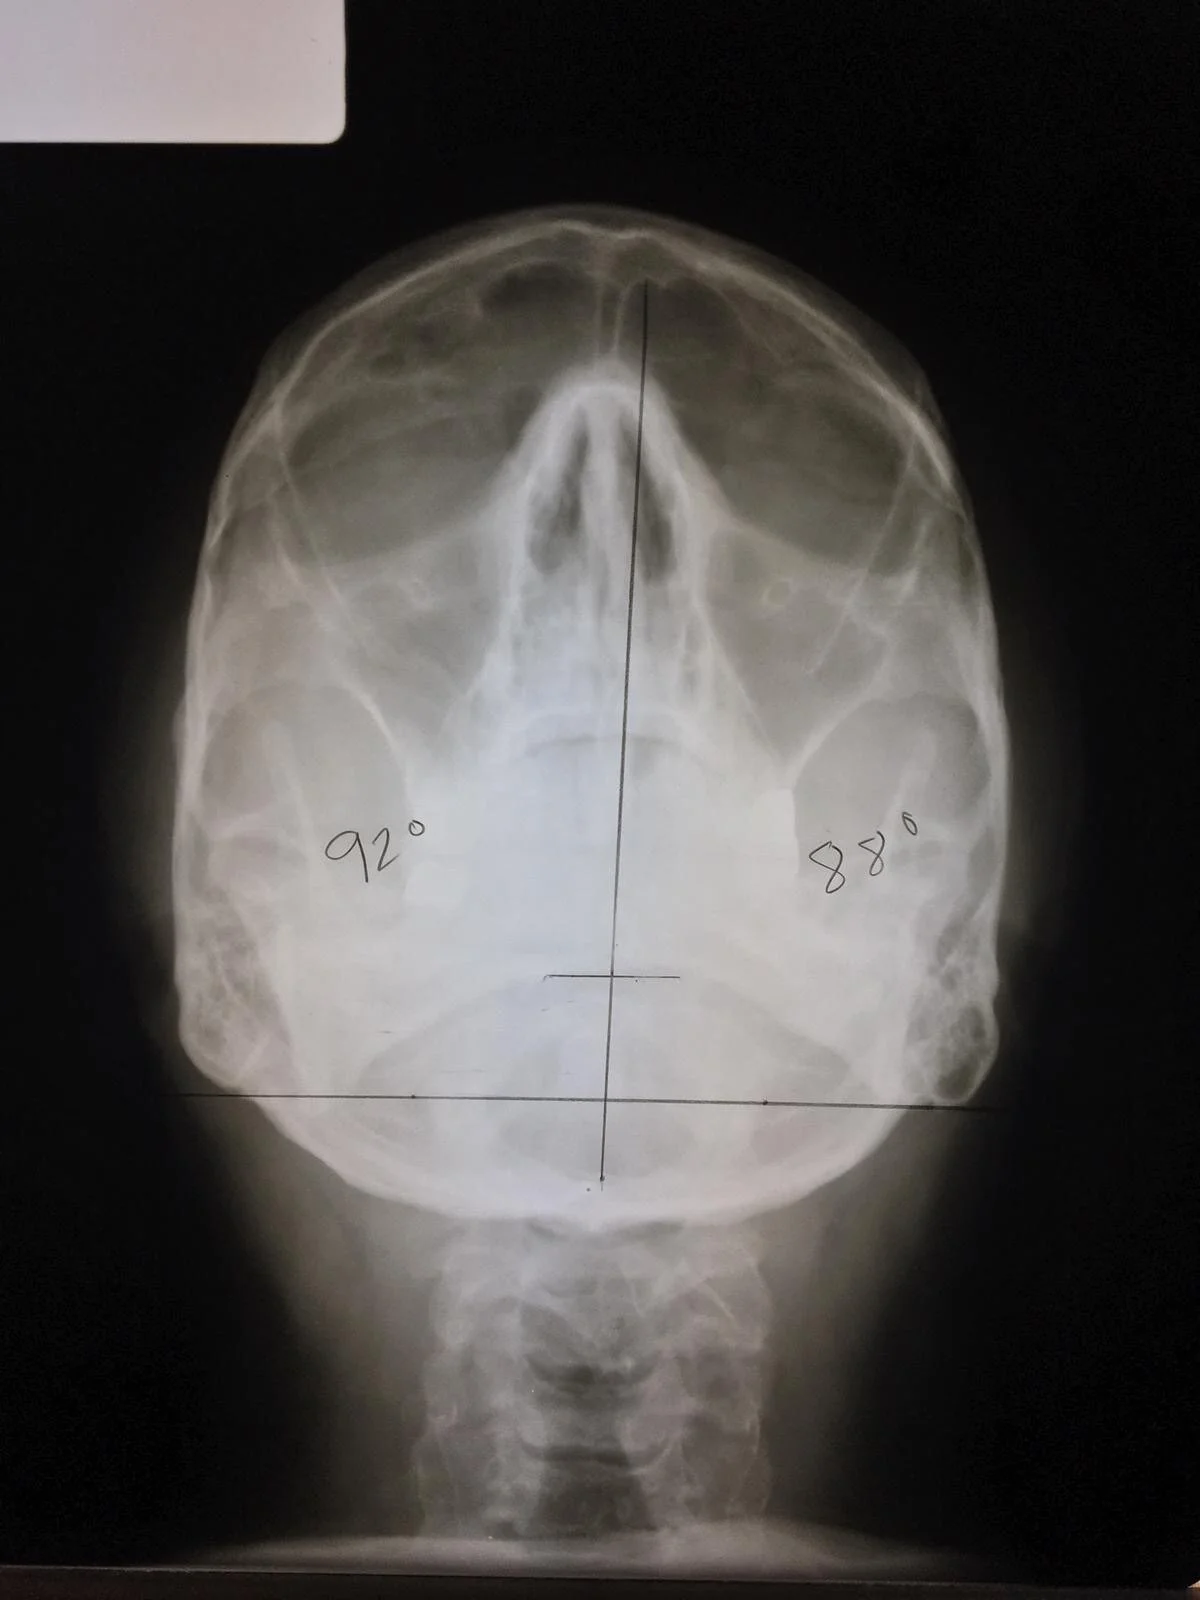

Base Posterior

With the Base Posterior, or BP for short, we look at the spine from superior to inferior (top to bottom) in order to discover the final components of the misalignment. For Atlas, we determine whether it has rotated anterior or posterior in relation to the foramen magnum. For the Axis on this view, we use the film to help confirm the previous findings from the other two films.